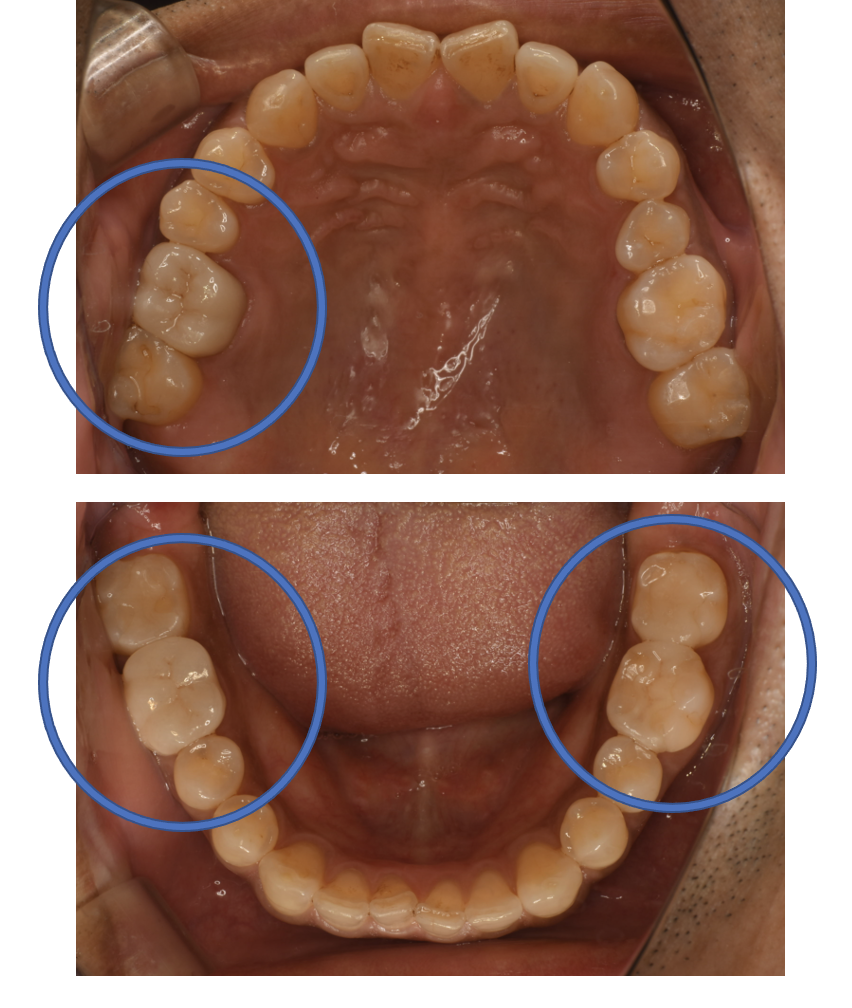

After

| 備考 | 院長より 銀歯の内部に虫歯が進行してしまっていたケースです。元々、大きい金属が入っている部位は、ジルコニアCrで被せ、比較的小さめの金属が入っていた場所は、セラミックInで詰めて対応したケースです。お口のなかが明るくなりました。 |